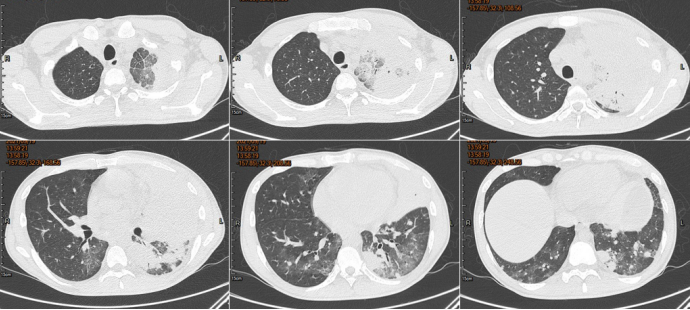

胸部CT

化验检查

血常规:Hb 75/L(↓),WBC 2.36×109/L(↑),NEU% 68.7%,PLT 167×109/L(↓)。

炎症指标:CRP 7.548 mg/dl,IL-6 66.02 pg/ml,PCT 0.216 ng/ml,ESR>140 mm/h。

G试验523.4 pg/ml,GM试验<0.25 μg/L。

呼吸道病原九项(-)。

细胞免疫B细胞18.63(90~560)(↓),CD4+T 360/μl(↓)(550~1440 /μl),NK细胞15.47 /μl(↓)(150~1100 /μl)。

体液免疫IgG 1940 mg/dl。

碱性磷酸酶226 U/L,γ-谷氨酰基转移酶263 U/L,乳酸脱氢酶306 U/L。

肿瘤标志物:血清铁蛋白2580 ng/ml(30~400 ng/ml)。

TB-spot A(-),X-pert(-)。